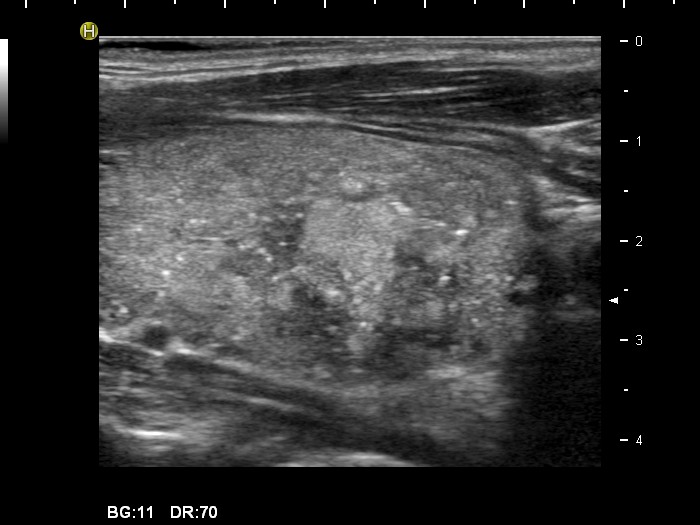

Hashimoto's thyroiditis with several cystic areas but without any nodules (histological diagnosis) - case 1365

There is no doubt of the origin of the hyperechogenic figure in the cystic lesion, this is a typical comet-tail artifact.

At first sight the interpretation of these figures seems to be difficult. However, this lesion is in the same patient whose other lesion is presented in the left images. It is reasonable to conclude that similarly bright figures within lesions presenting an identical echo pattern have the same origin.